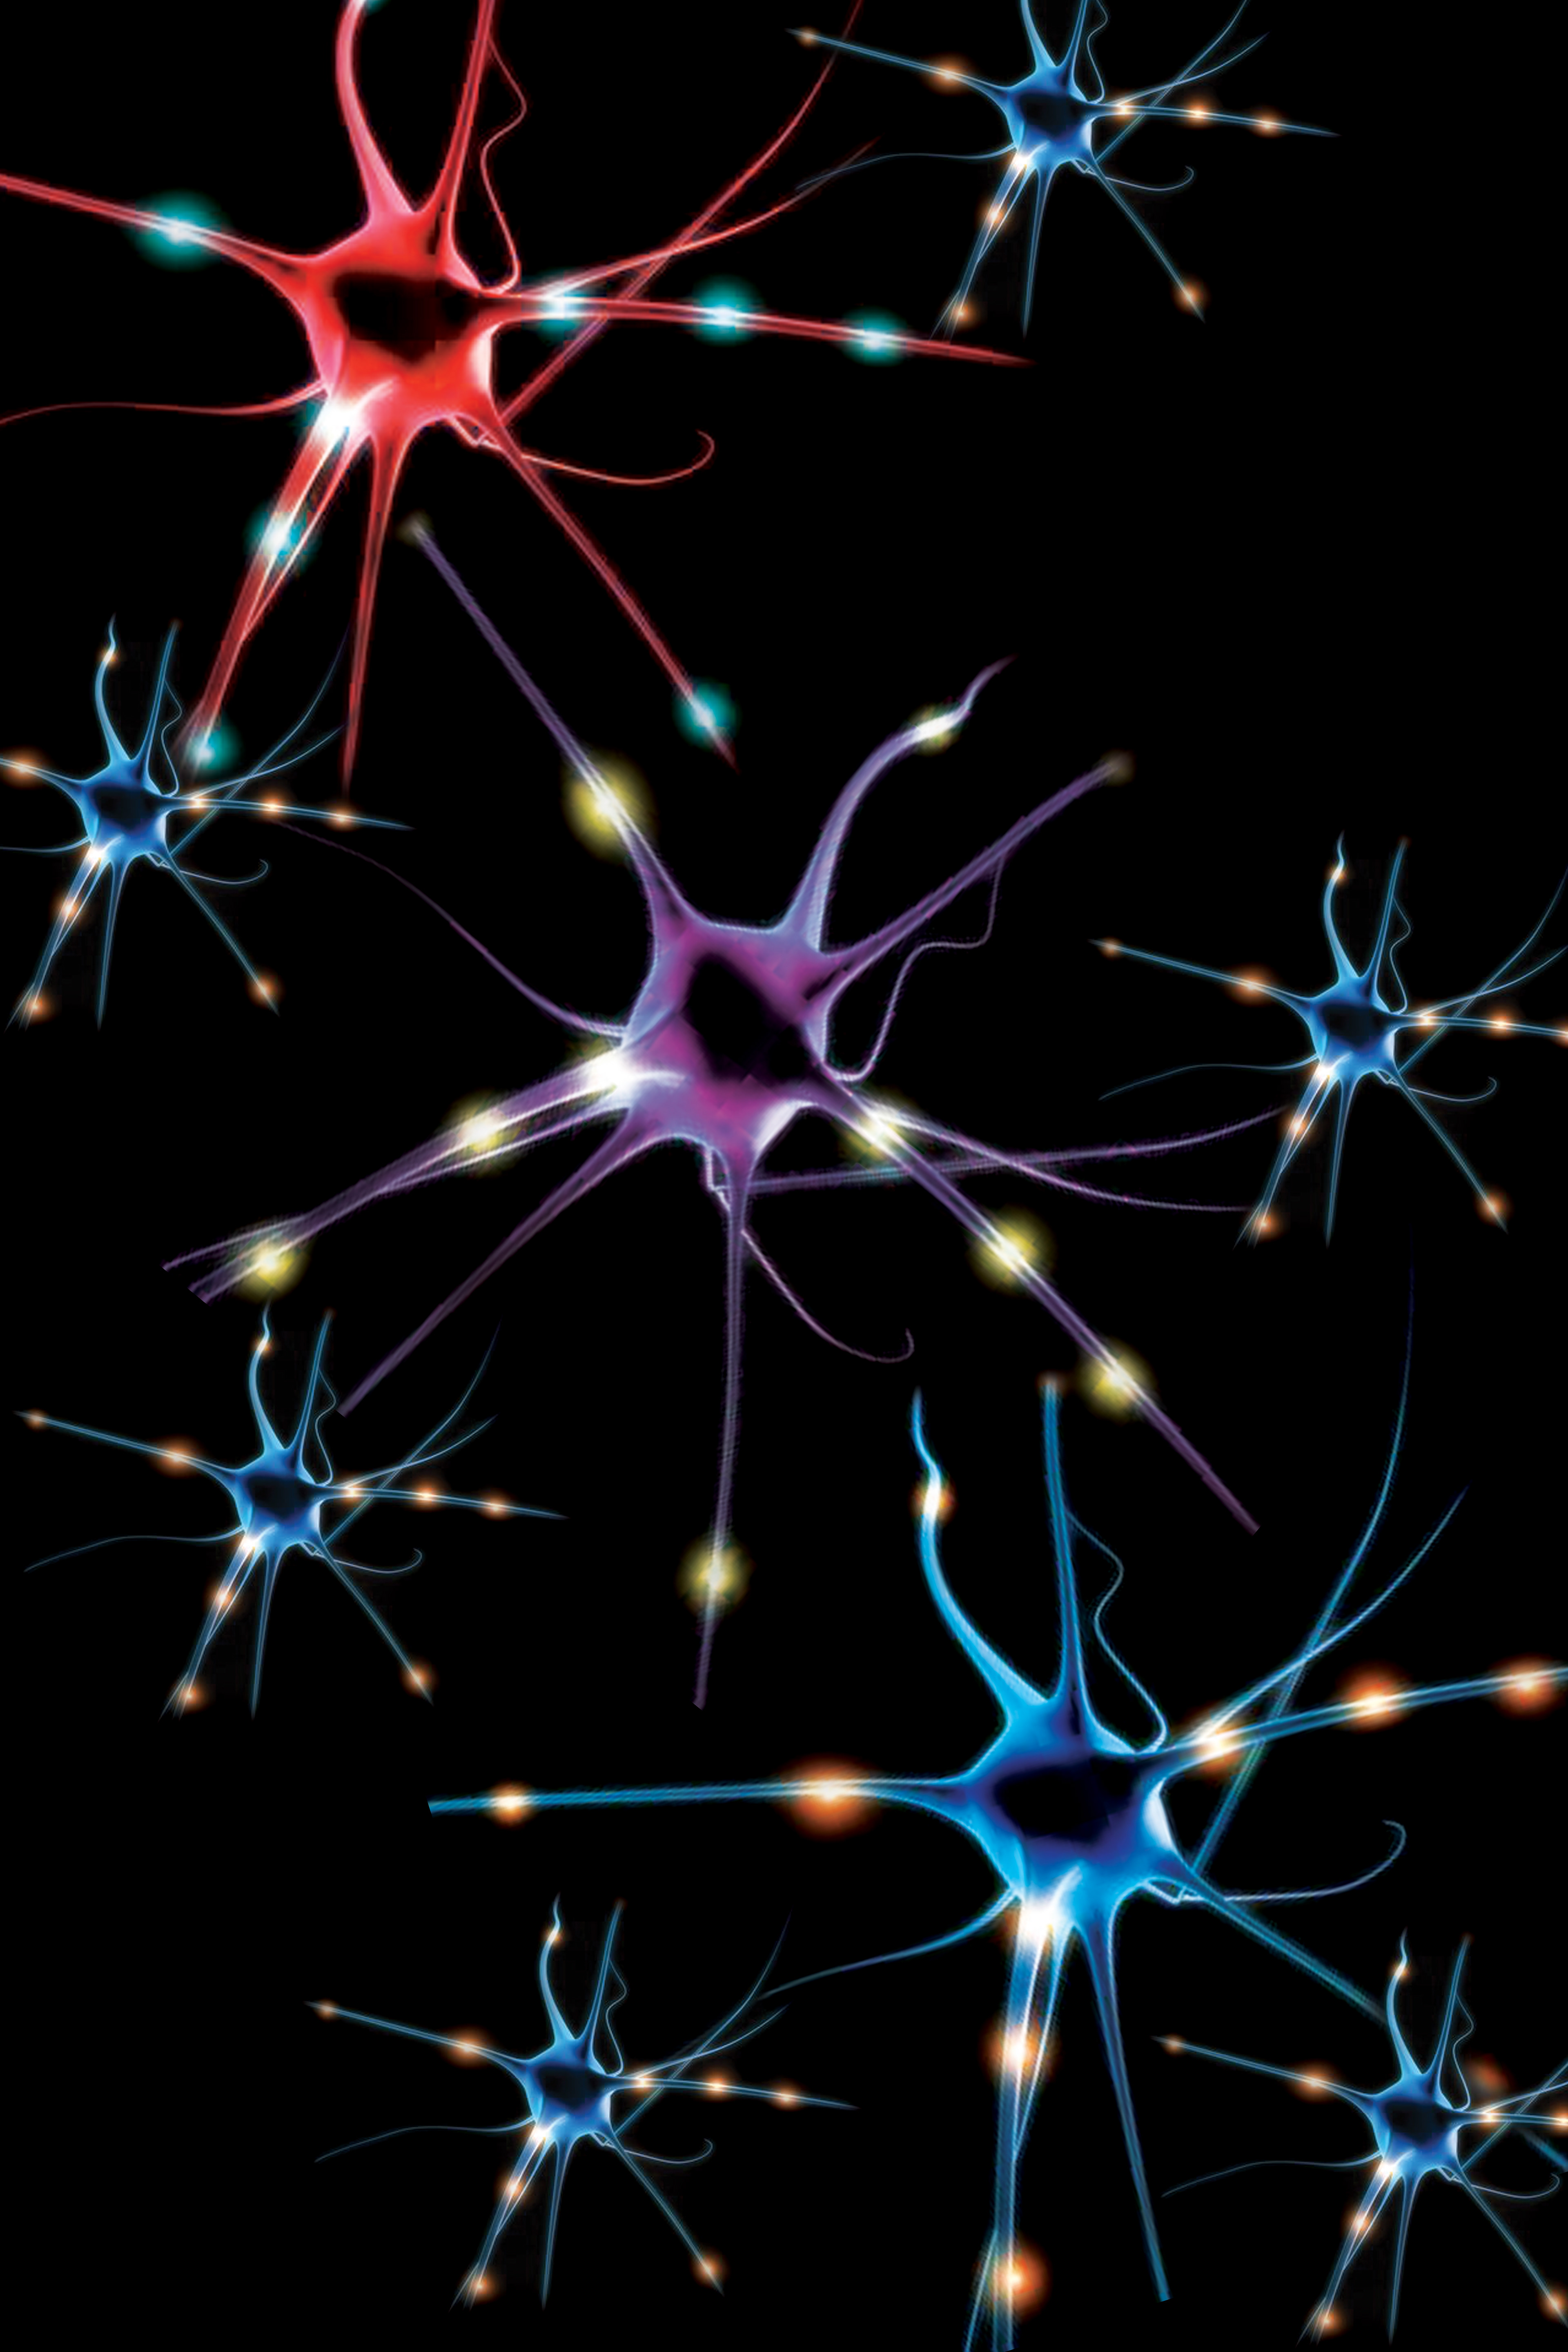

The Migraine Pack Lid Imagery

Color Palettes and Illustration Examples

What are the Spots?

If you've ever rubbed your eyes a little too long, you know that you can see colors (phosphenes) due to the eye perceiving light that isn't actually there. For many people, optical migraines can come with colorful dots, black streaks, or white waves. Migraines are something that you cannot see, but optical migraines and aura migraines provided an interesting take for the visual imagery.